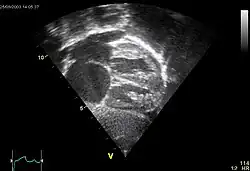

Echocardiography

In transthoracic echocardiography, an atrial septal defect may be seen on color flow imaging as a jet of blood from the left atrium to the right atrium.

If agitated saline is injected into a peripheral vein during echocardiography, small air bubbles can be seen on echocardiographic imaging. Bubbles traveling across an ASD may be seen either at rest or during a cough. (Bubbles only flow from right atrium to left atrium if the right atrial pressure is greater than left atrial). Because better visualization of the atria is achieved with transesophageal echocardiography, this test may be performed in individuals with a suspected ASD which is not visualized on transthoracic imaging. Newer techniques to visualize these defects involve intracardiac imaging with special catheters typically placed in the venous system and advanced to the level of the heart. This type of imaging is becoming more common and involves only mild sedation for the patient typically.